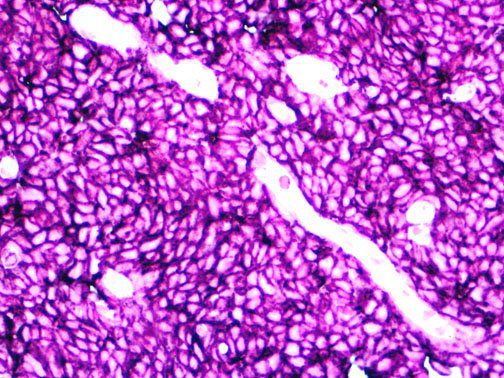

The first cytokines released are interleukin 1β (IL-1β) and tumor necrosis factor-α (TNF-α), which attract a variety of circulating white blood cells (WBCs) to the infection site, including neutrophils, monocytes, macrophages, and natural killer (NK) cells. This response, along with the antipathogenic chemicals released by these cells (i.e., complement), comprise the innate immune response. These cells directly attack the invading pathogen and also release additional cytokines, chief among them interleukin-1 and 6 (IL-6). IL-6 is essential for invoking the adaptive immune response, which calls T-cells, B-cells, and T helper (Th) cells to the infection site. IL-6 also stimulates further recruitment, proliferation and activation of macrophages.

It is the ICU physician who is most likely to witness one of the deadliest manifestations of the abnormal immunological response, the cytokine storm syndrome (CSS). This response is also referred to by some as the cytokine release syndrome (CRS). CSS is characterized by continuous activation and expansion of macrophage and lymphocyte populations, which secrete large amounts of cytokines, causing the cytokine storm. This massive cytokine release is akin to hemophagocytic lymphohistiocytosis (HLH) disease, a syndrome characterized by initial unchecked and persistent activation of cytotoxic T lymphocytes and NK cells.